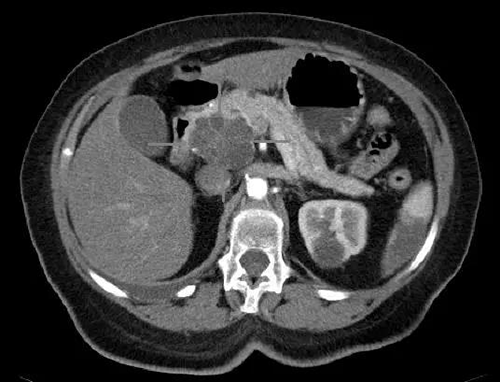

ÒÈÍ·°©ºÍÄÒÏÙ°©¾ßÓÐiv±ÈÕնȵÄÖáÏòCTͼÏñ£¨Í¼Æ¬ÈªÔ´:Science£©